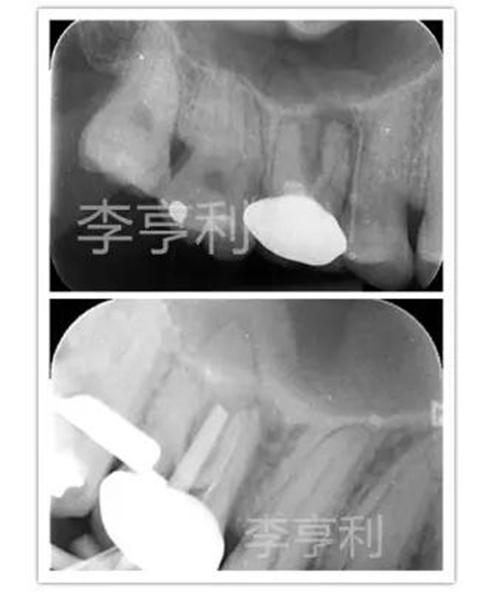

16由于出現(xiàn)瘺管,被轉(zhuǎn)診醫(yī)生診斷為慢性根尖膿腫并開(kāi)始根管治療。醫(yī)生只能疏通MB到根尖,其它根管均鈣化不通,故轉(zhuǎn)至我處 (圖上)。

當(dāng)重新打開(kāi)患牙時(shí),P根和DB的冠1/3已經(jīng)被轉(zhuǎn)診醫(yī)生在探尋根管時(shí)大范圍破壞,而且在顯微鏡下仍未能找到根管。隨后告知患者16較差的根管消毒和預(yù)后,但患者表示強(qiáng)烈保存患牙的欲望。故決定進(jìn)行根管治療,但出于對(duì)剩余牙體組織的保存,僅預(yù)備通暢的MB2和擴(kuò)大MB的根尖預(yù)備,不再嘗試疏通DB和P (圖下)。

術(shù)后片顯示除MB根充填能達(dá)根尖部,DB和P的根充物都欠充且錐度過(guò)大,單純技術(shù)要求來(lái)看,這是不及格的根管充填 (圖左);

1年回訪發(fā)現(xiàn)16瘺管完全消失,X片也能觀察到明顯的根尖暗影縮小 而且患牙也無(wú)任何主觀癥狀,且能正常進(jìn)行咀嚼,所以從臨床角度來(lái)看,這能視為成功的根管治療 (圖右)